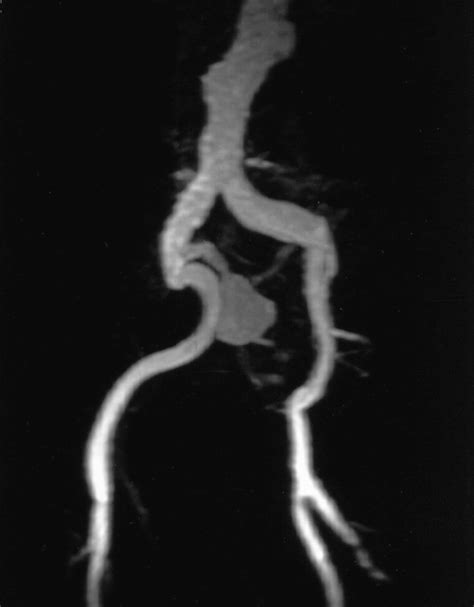

• Magnetic Resonance Angiography (MRA): This test uses magnetic fields and radio waves to create images of the blood vessels, providing information similar to CTA but without radiation exposure.

• iliac artery aneurysm radiology